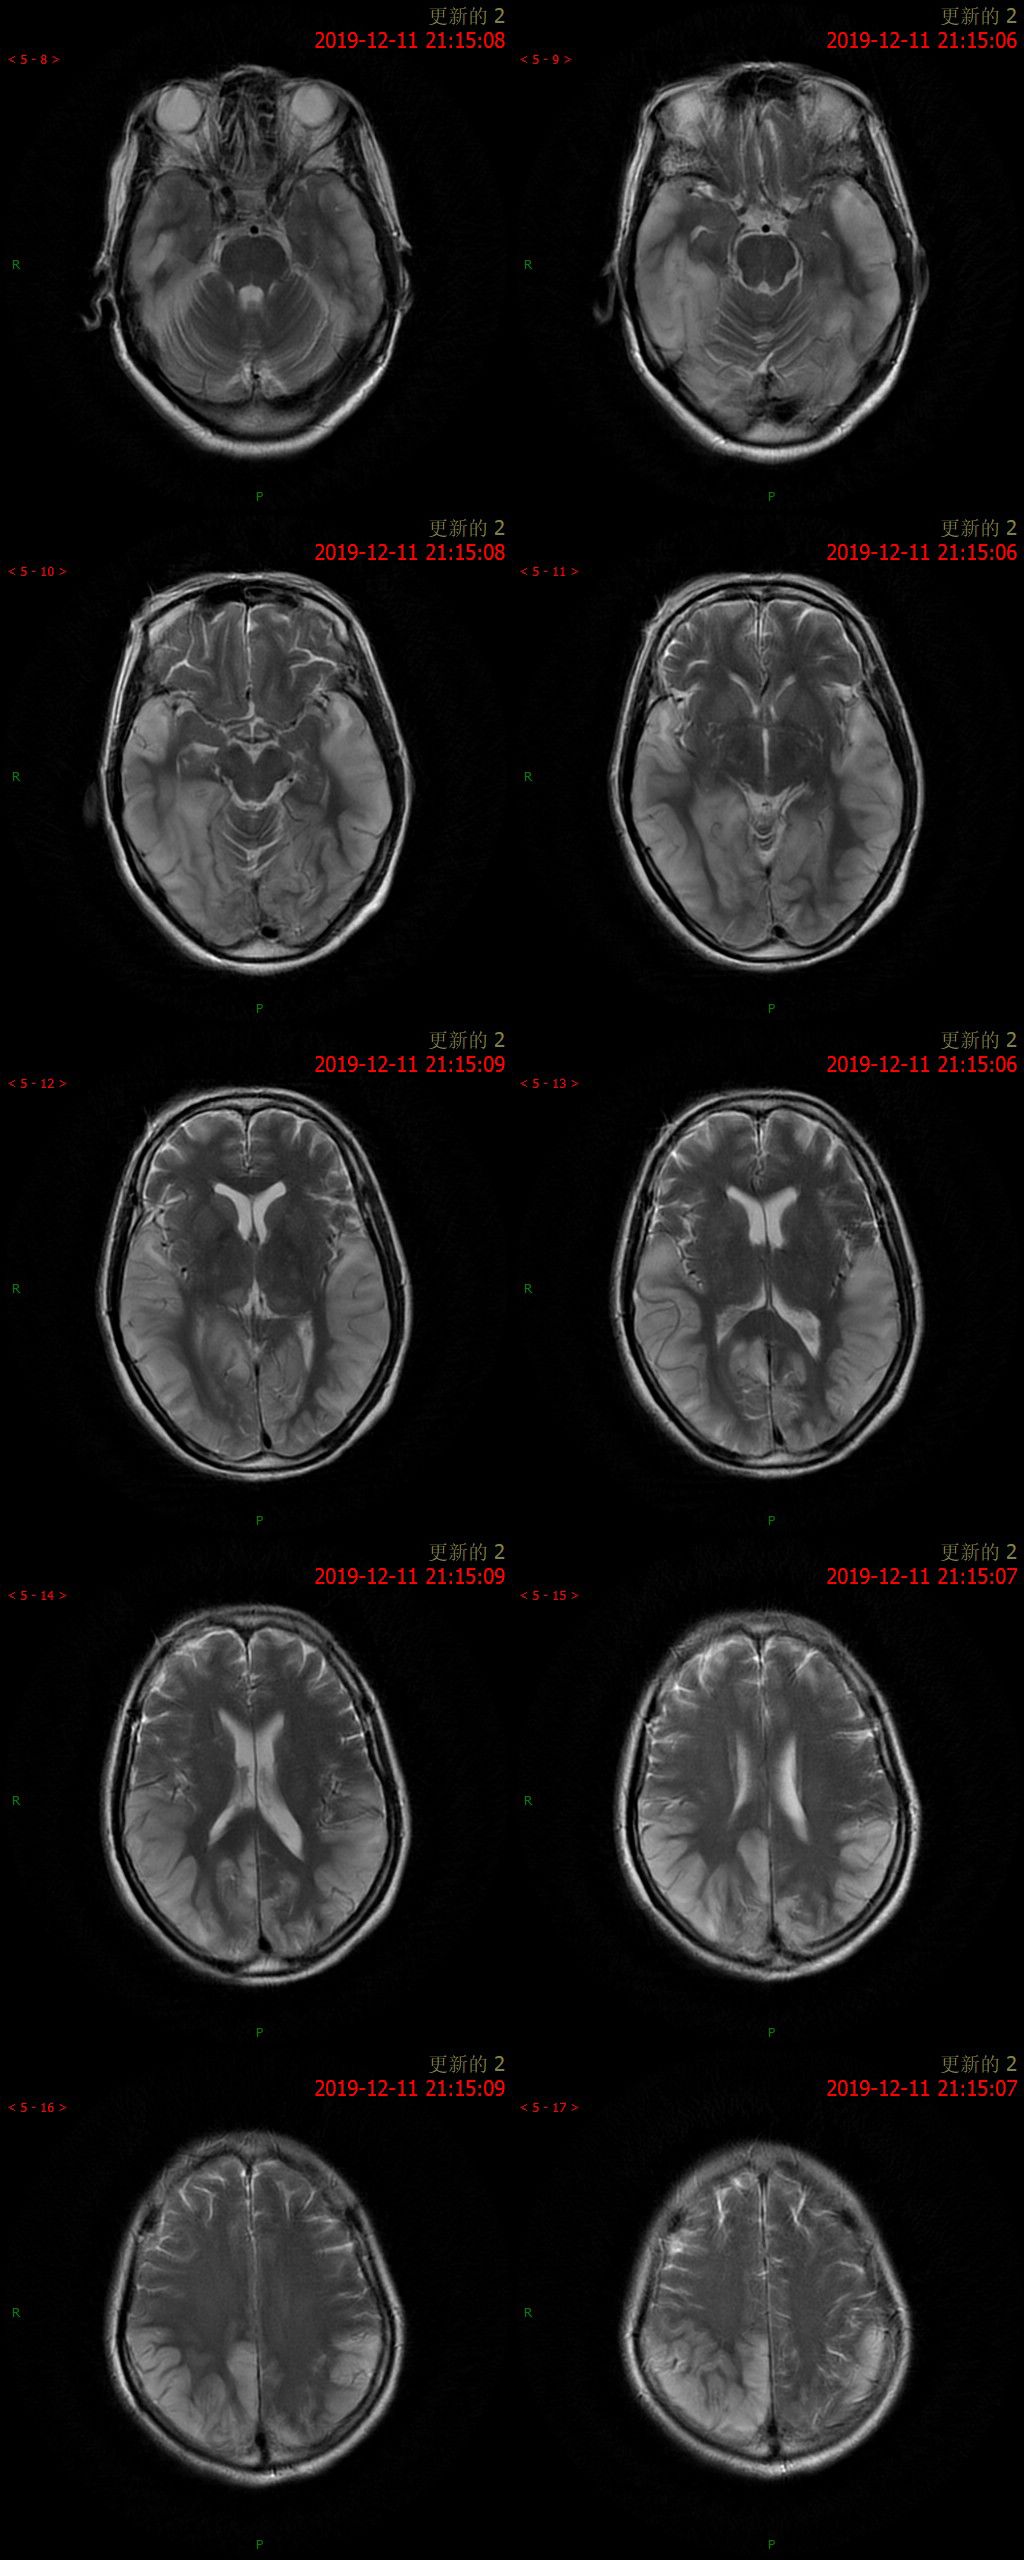

12.11 日 MR 平扫

患者为中年女性,临床症状不重,影像表现明显。双侧大脑半球多发病变,DWI 呈高信号,呈非对称性分布,且病灶分布呈跨血管支配区分布,DSA 为正常表现,可以排除脑梗死。短期内病灶迅速进展,MRS 可以看到明显倒置的乳酸双峰,考虑 MELAS。

①以大脑皮质灰质损害为主, 多累及半球后部颞顶枕叶,其次为颞叶、海马和海马旁回、额叶、小脑等,呈游走性、多变性、此起彼伏等表现;其特点是不按解剖血管分布, 累及皮质和皮质下白质, 可见皮质的层状异常信号;

②对称性双侧基底节、丘脑, 脑干等灰质核团损伤的异常信号;由于灰质核团的细胞代谢活动比白质纤维强, 容易受累;

③灰质和白质散在的异常信号;白质病变多侵犯较新的周围白质, 即皮质下和三角区后部白质。